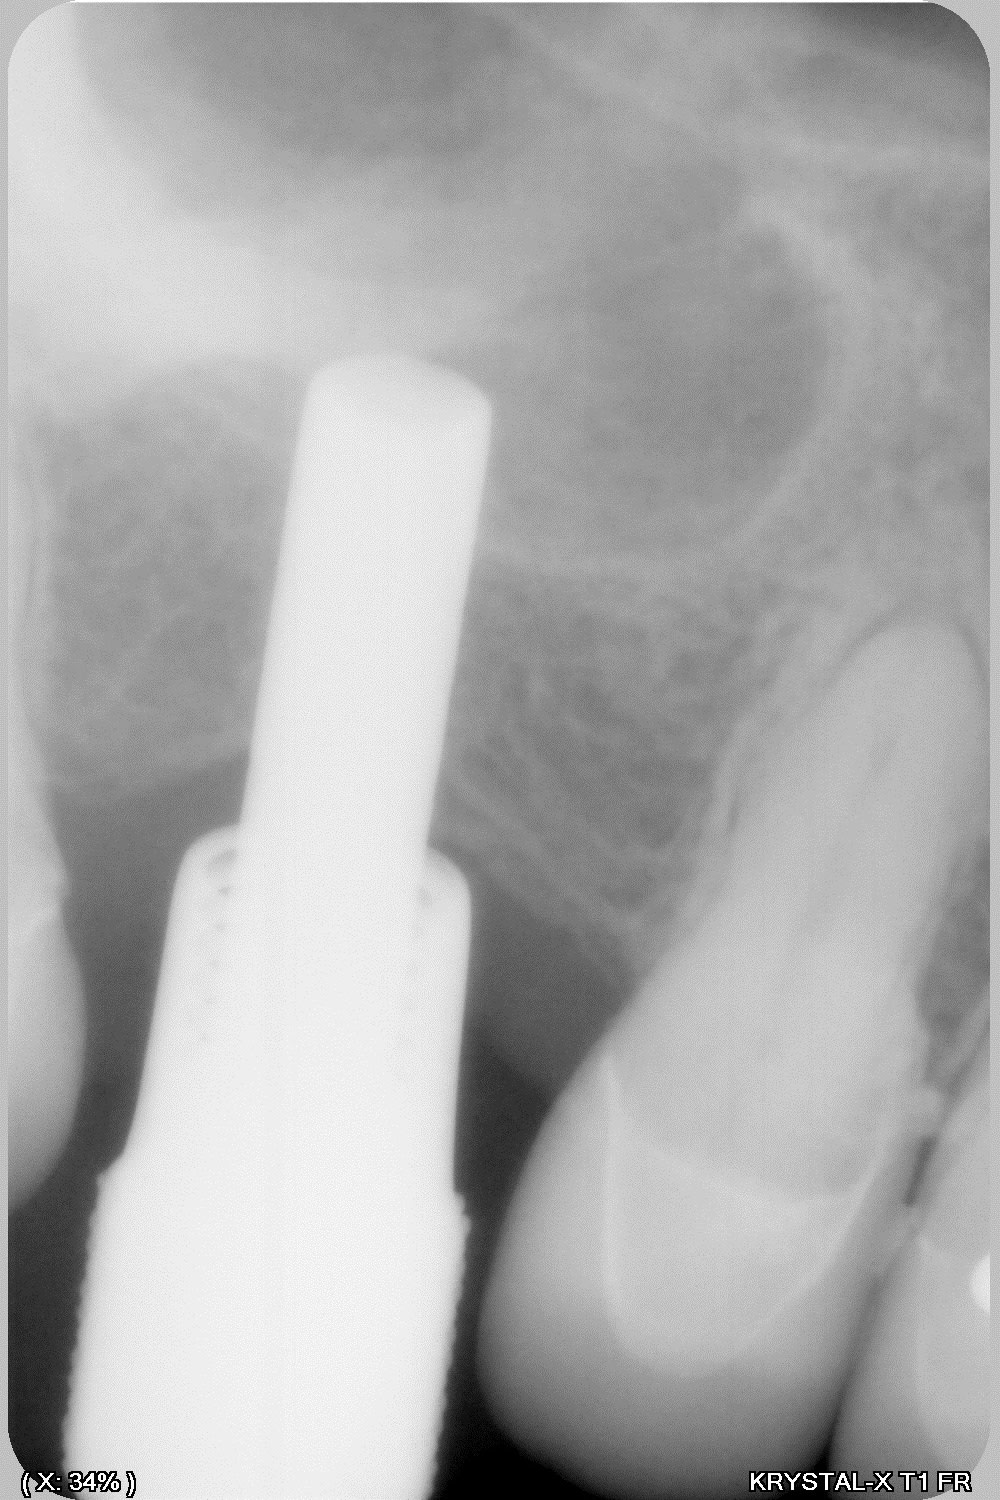

14/01/2020 à 13h00

donc tu avais raison Enlaye... le bridge à cassé (sur un carambar quand même:-))

dépose, nettoyage sablage des couronnes récupérable et pose d' implant, uniquement en manuel (os tendre)

ben oui ç était prévisible , à cause des 2 flèches bleues plus haut .

ç est un grand classique ça . quand tu ne peux pas être libre devant , tu t énerves derrière .

et ç est meme pas derriere en fait , mais plutôt dans une zone la plus éloignée possible de devant .

donc ç est derrière et de coté . en diagonale , quoi .

il s avère qu en plus là, derrière , ç est nouveau bridge , donc pas encore usé à sa convenance , tout au moins en latéral .

alors elle s engatse dessus avec beaucoup de force puisque ç est tout pres de l axe charniere .

là où ç est vicieux , ç est que si ton bridge etait pipé avec une grosse erreur occlusale , ben il serait tjs là , entier .

il serait tjs là , pcq si l erreur était plus importante à l arrière ,sur un bridge à la con , elle aurait eu mal soit a l atm soit aux dents antagonistes , et elle aurait cherché un autre endroit pour aller se désénerver . en l occurrence elle t aurait fracassé le bloc ant .

alors maintenant que tu a résolu le pb post ( qui n était qu une conséquence de devant ) méfies , par sympathie pour toi , je te conseillerais de vite vite retoucher au niveau des 2 flèches bleues .